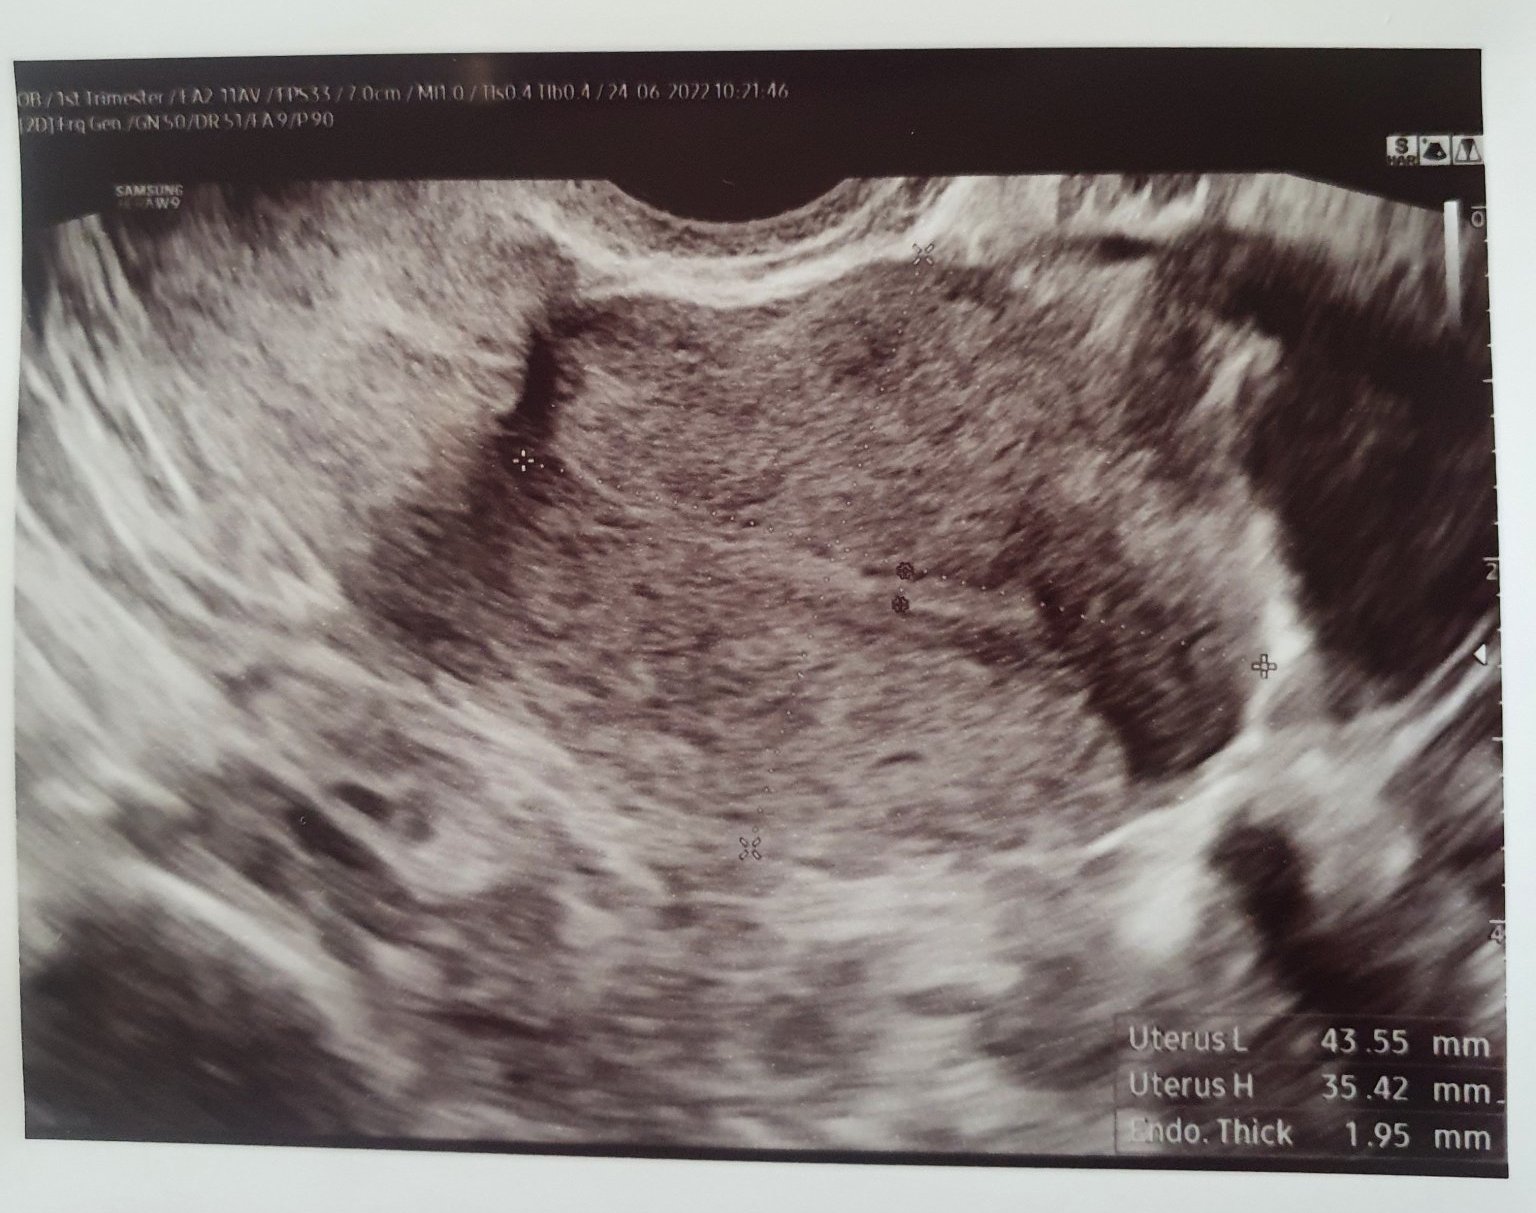

Ето снимките от двата прегледа:

Скрит текст:

Доклад - няма нищо в матката, лигавицата е като след цикъл, НО до десният чйчник визуализира нещо с "инензивна васкуларизация" - пуснахме контролно чхг, за да в сигурна, че не е извънматочна. Макар да каза, че обикновенно дори и да е зивънматочна се визуализира жълто тяло и лигавицата си остава набъбанала.

Виждаше се, и аз го видях, но каза, че е с неправилна форма и според нея не е закрепен.

Сега ясно се виждаше, че лигавицата е тънка та тънка....

Реално не се вижда нищо в матката и лигавицата е като за след цикъл.